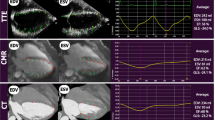

4D flow magnitude datasets were multiplanar reconstructed in LV 2-chamber and 4-chamber view cut planes, as well as a stack of 11-14 contiguous short-axis slices (slice thickness, 8 mm) covering the entire LV cavity using standard software (cvi42, Circle Cardiovascular imaging) to obtain 4D flow-cine series for further evaluation (Fig. 2a).

Pre-processing and evaluation of native 4D flow magnitude data. Multiplanar reconstruction of 4D flow-cine series in 4-chamber, 2-chamber and short-axis views (a): The 4-chamber view was reconstructed through the center of the mitral and tricuspid valve in a basal short-axis cut plane (left panel). The LV 2-chamber view was orientated parallel to the left-right ventricular insertion points positioned in the center of the LV cavity (mid panel). Stacks of short-axis images covering the LV were reconstructed in the end-diastolic phase (right panel). LV segmentation in short-axis images with exclusion of the papillary muscles and trabeculae from the blood pool from 4D flow-cine (b, left panel) and bSSFP-cine (b, right panel). LA segmentation in long-axis images from 4D flow-cine (c, left panel) and bSSFP-cine (c, right panel). Multiplanar reconstruction and segmentation of pulmonary artery cross section for evaluation of pulmonary artery net forward volume (NFV) (d)

All evaluated images received a quality score ≥ 3. Examples with overall excellent image quality scores are shown in Fig. 3a and b. Average image quality scores for 4D flow-cine and bSSFP-cine images are given in Table 2 and demonstrate differences in systolic short-axis as well as systolic 4-chamber view images. Representative examples of systolic 4D flow-cine short-axis and systolic 4-chamber bSSFP-cine images with lower image quality scores are shown in Figures 3c and 3d, respectively.

Representative examples of images with adequate to excellent image quality scores. End-diastolic and end-systolic LV 2-chamber, 4-chamber and short-axis images in 4D flow-cine (a) and bSSFP-cine (b) series with excellent quality scores. 4D flow-cine short-axis images of adequate quality (c). bSSFP-cine images (3T off-resonance band in the left atrium is marked by arrow) of good quality (d).